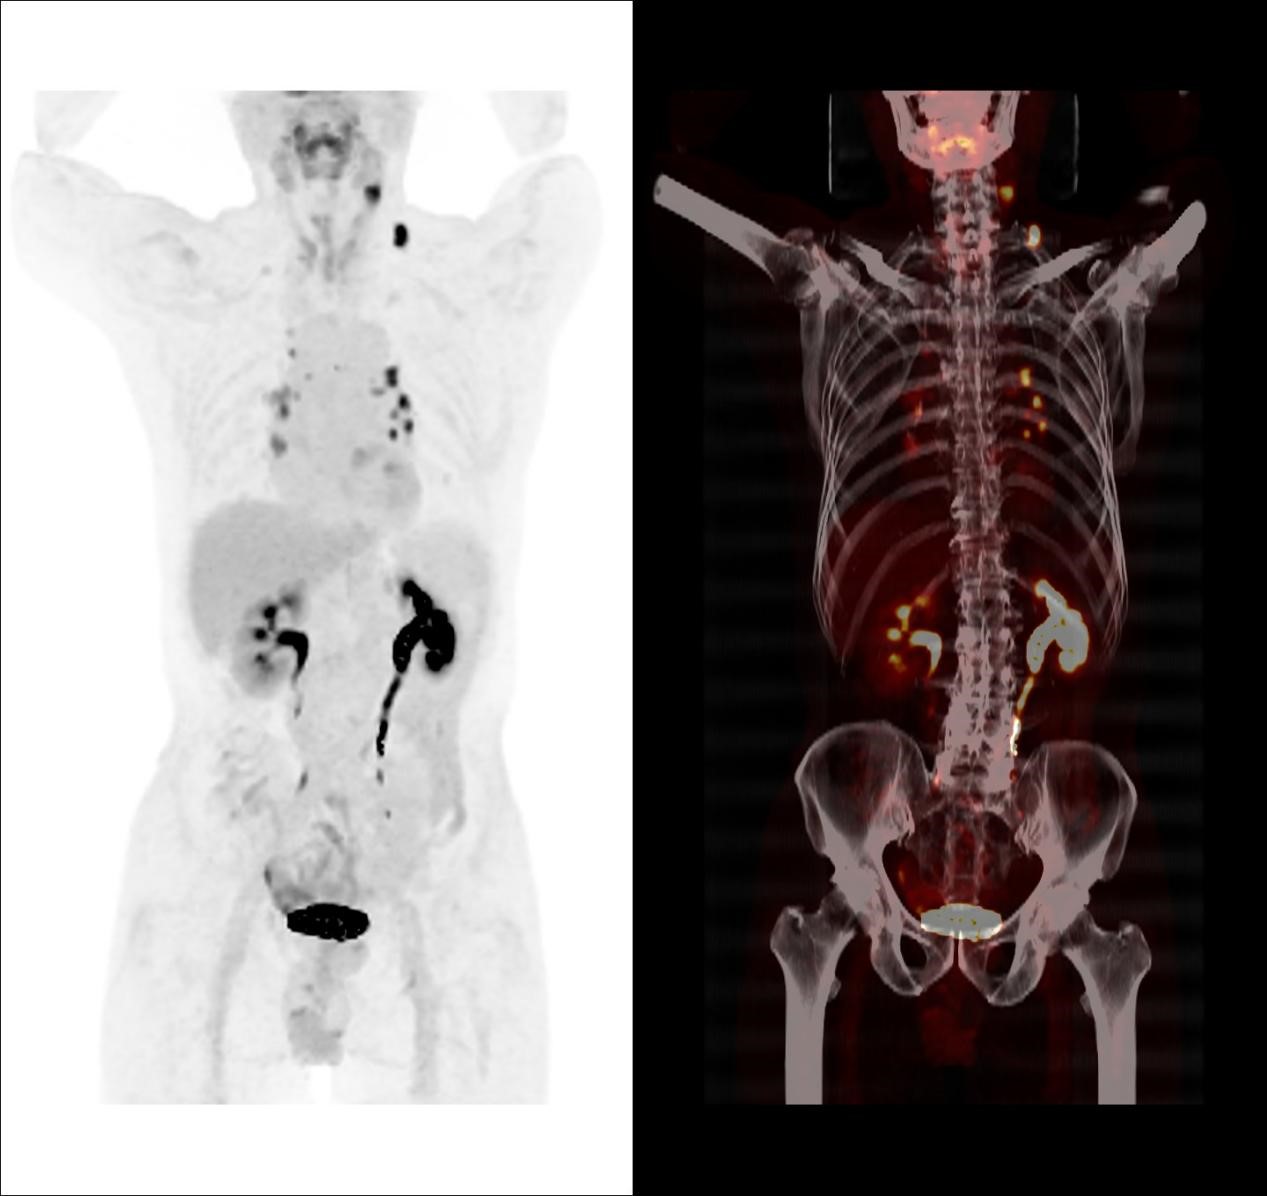

因此,临床医生给患者进行了传统的颈胸部增强CT检查以了解术后颈部情况,并试图寻找可能存在的原发病灶,但令人遗憾的是,增强CT并没有发现原发灶及转移相关证据。于是,医生决定给患者做一个全身PET/CT检查。

随着现代医学的不断发展,除了B超、CT、MRI等影像检查外,PET/CT也逐渐进入大众的视线并普及应用。PET/CT,全称正电子发射计算机断层显像,它是PET和CT的结合,既可以像CT一样为病灶提供精细的解剖和病理信息,又可以提供病灶的功能和代谢等分子信息,两者完美结合,优势互补,真正实现了1+1>2。

对于贺老伯来讲,超声及颈胸部增强CT检查均未能发现颈部、纵隔及肺门异常淋巴结,而PET/CT准确地找到这些异常淋巴结,就像多盏灯将这些隐藏的可疑淋巴结点亮一样,让可疑病灶无处遁形,为临床确定精准治疗方案提供帮助。